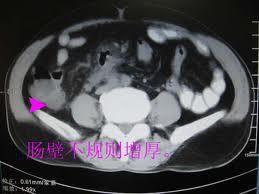

2.皮肌炎時小腸有不同程度的擴張及分節變化、伴低動力和通過時間延長。肉眼可見腸壁水腫、增厚。鏡檢示多處黏膜糜爛、黏膜下層水腫、肌層萎縮和纖維化伴淋巴及漿細胞浸潤。腸管黏膜下層至漿膜層小動脈、小靜脈內膜增厚易有血栓形成及管腔閉塞。

2.皮肌炎時小腸有不同程度的擴張及分節變化、伴低動力和通過時間延長。肉眼可見腸壁水腫、增厚。